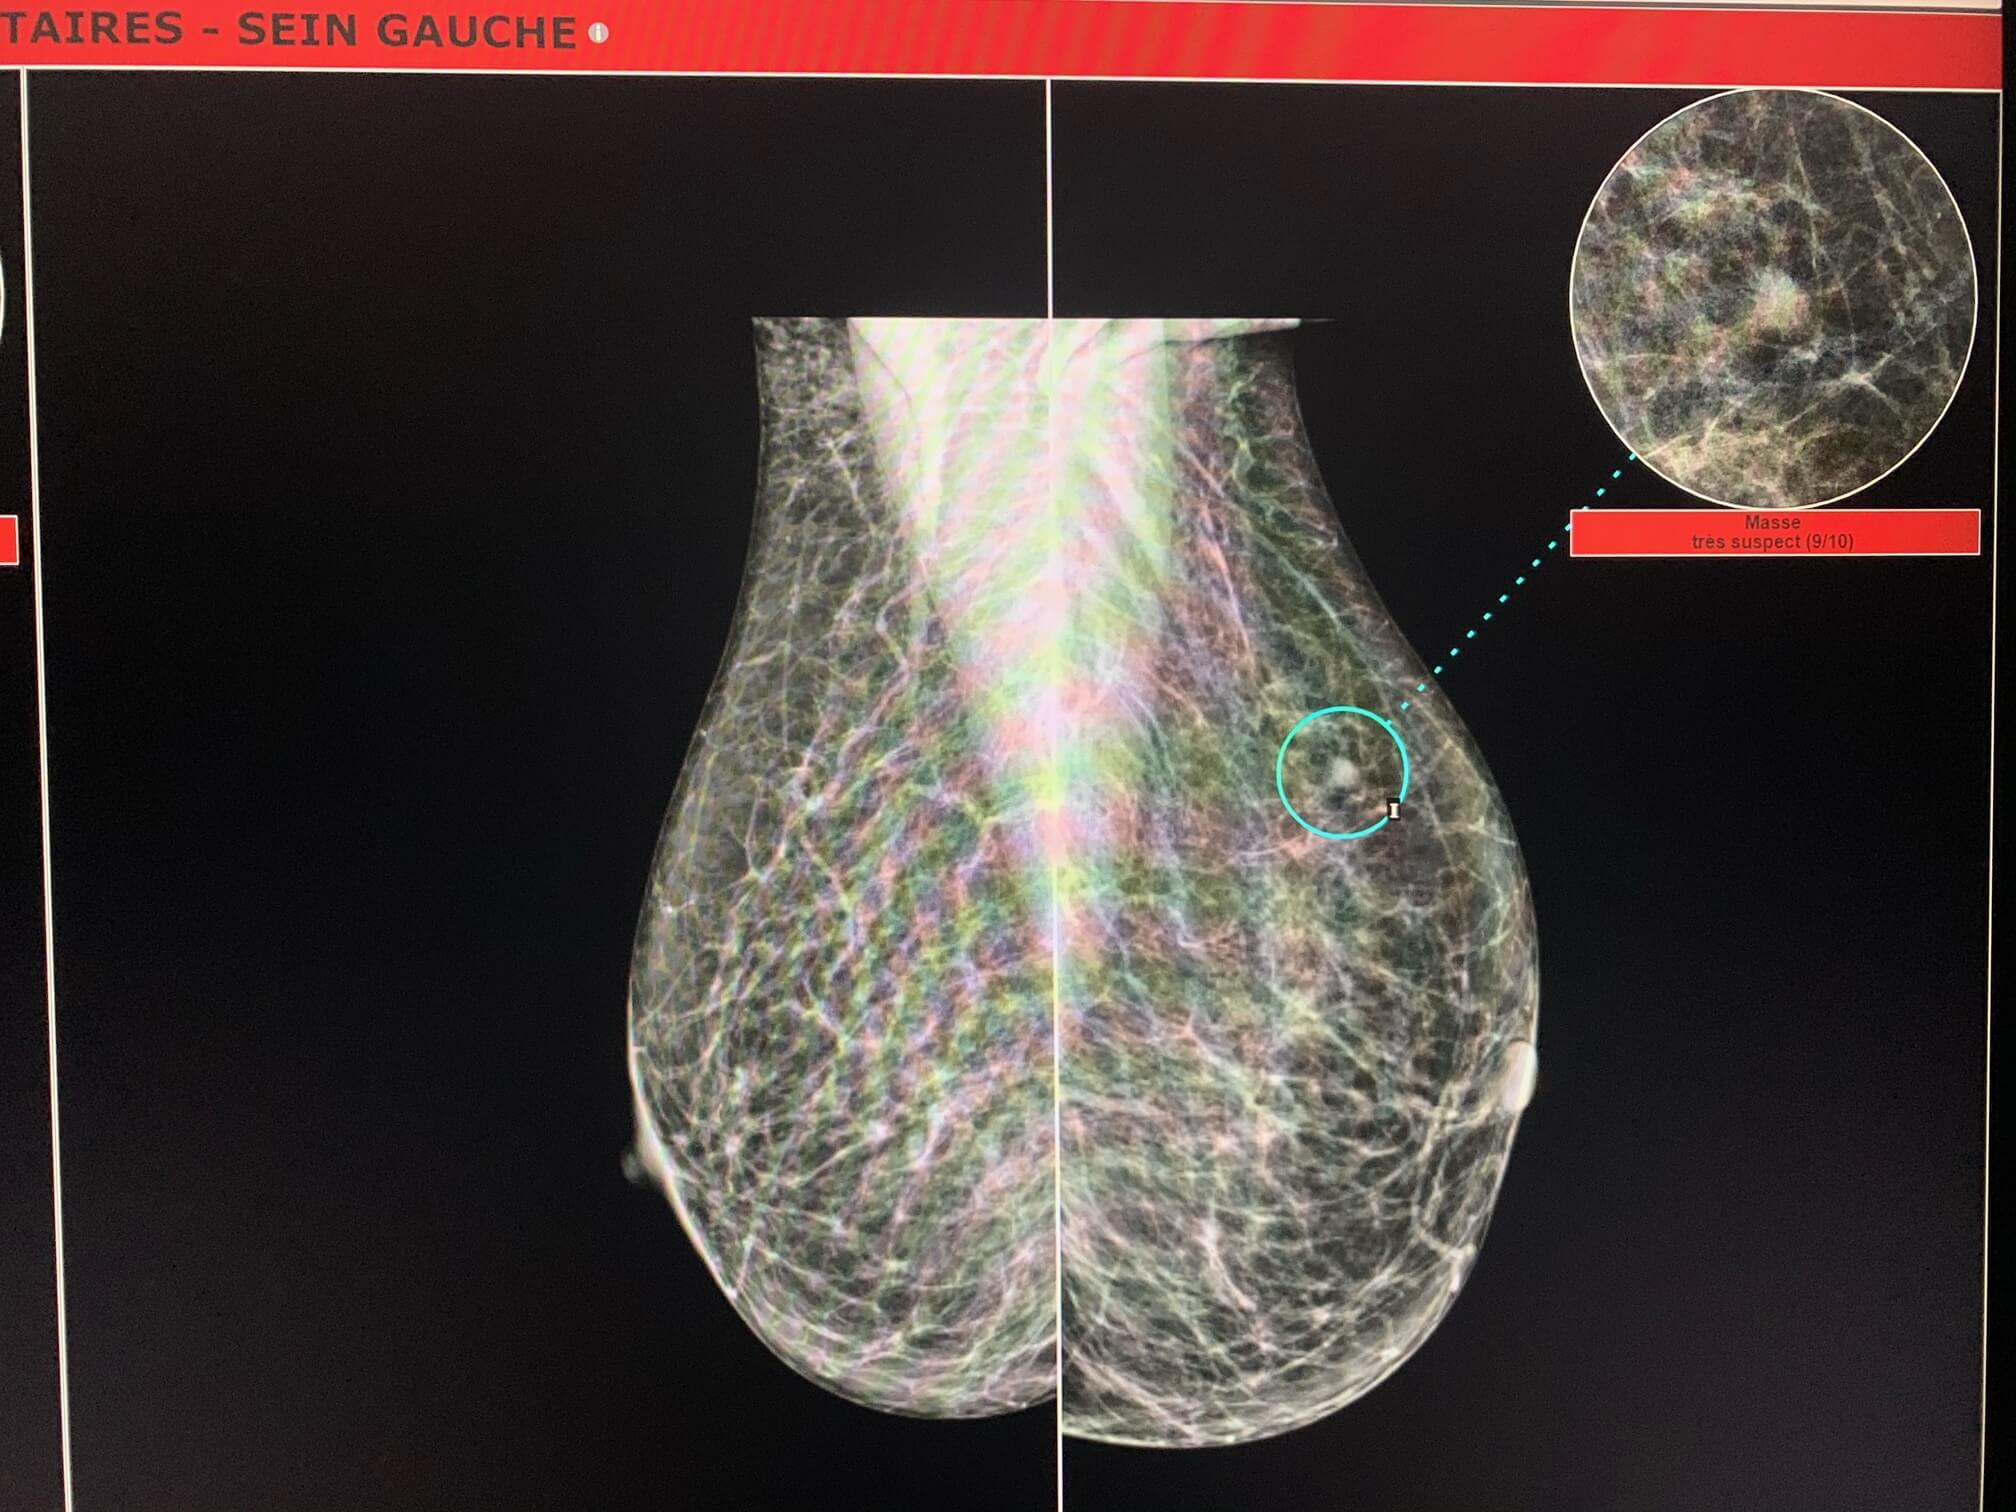

MammoScreen™ pointe une lésion du quadrant supéro-externe du sein gauche.

En rétrospectif, l’analyse par MammoScreen de la mammographie de 2018 interprétée normale par le premier et deuxième lecteur pointe la lésion sur le cliché oblique gauche.